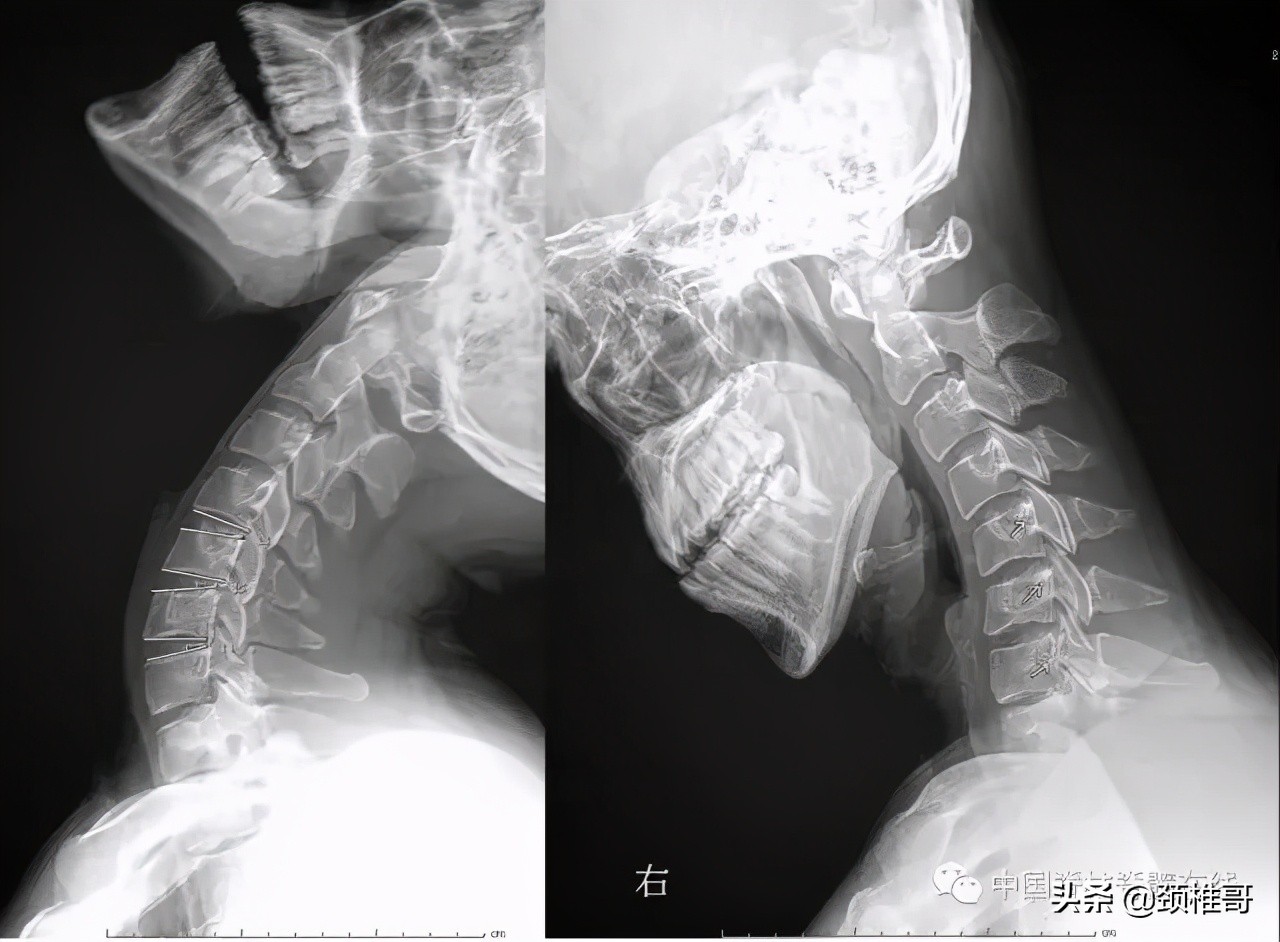

脊髓型颈椎病是一种最严重类型的颈椎病,是在肌肉、韧带、椎间盘、骨和关节都已经发生退变,颈椎动态不稳和静态不稳同时存在,代偿性的增生、钙化、韧带肥厚等综合作用下,椎管狭窄,脊髓受压所导致的一种类型颈椎病。在慢性压迫的基础上,轻度的外伤就会导致瘫痪,有的病人甚至在咳嗽、喷嚏后发生瘫痪。因此,这型颈椎病需要把握手术时机,该手术时尽早手术,否则,一旦发生瘫痪之后,四肢感觉运动、大小便功能很难恢复。在手术之后,一定进行正规的康复,否则,在手术部位的相邻节段还会继续发生退变、不稳、增生、脊髓受压等而需要一而再,再而三的手术。

脊髓型颈椎病患者会在轻轻受伤之后发生瘫痪